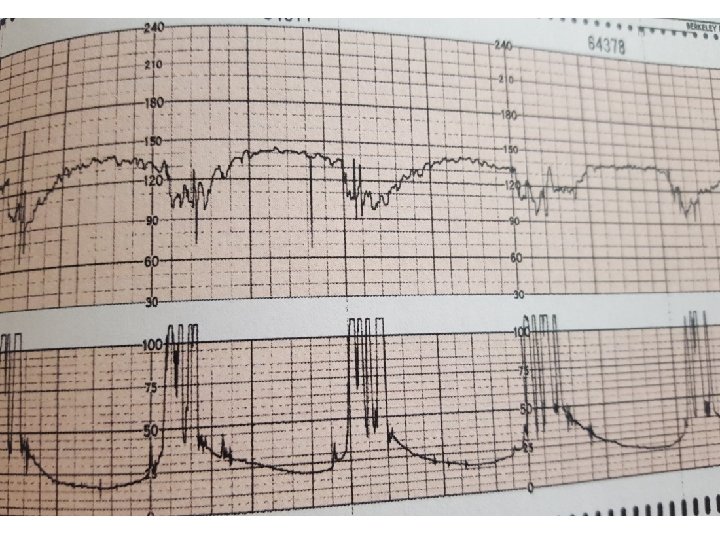

Causes of cord compression pattern • • Oligohydramnious Dilatation 8 -9 cm Rapid descending True umbilical cord prolapse(rare)

Complicated variable deceleration Indicated fetal hypoxia • Tachycardia • Lack of variability • Slow return to baseline • Large amplitude(to 60 bpm or duration 60 second) • Loss of pre and post shouldering • Smooth overshoot